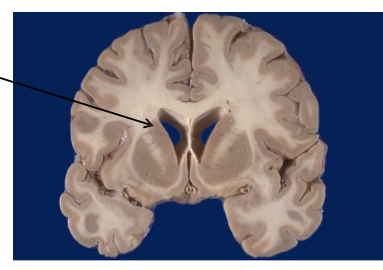

Explain which tissue contains gray and white matter.

Cerebral cortex is outer gray matter; cerebral white matter contains axon tracts.